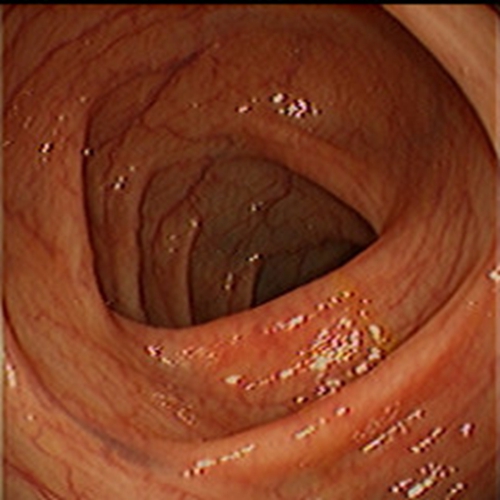

急性胃炎圖片

急性胃炎